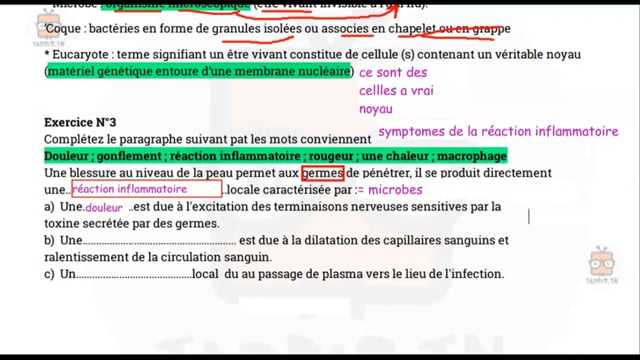

Sciences SVT

1ᴱ̀ᴿᴱ année

Enregistrement 2020-2021

Enregistrement 2021-2022

Enregistrement 2022-2023